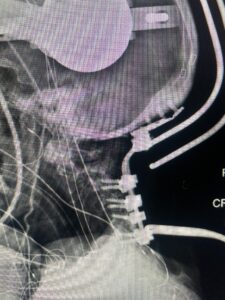

Cervical x-rays revealed a significantly increased atlanto-axial interval (Fig. 5) On review of her imaging studies it was noted that the right C2 isthmus was very thinned by the vertebral foramen (Figs 6a, b, and c) which would make an attempt at placing a C2 pars screw dangerous. A decision was made to perform an occipital-cervical fusion because only possible unilateral fixation and an extensive C1 laminectomy to be performed eliminating a fixation point if a more traditional C1-C2 was performed. Even if C1 lateral mass screws were able to be placed one could only perform a unilateral screw construct fixation to C2. We performed an occipital cervical fusion down to C4 to get enough inferior fixation and C1 laminectomy. The decompression went well. We placed a left unilateral pars screw and bilateral C3 and C4 lateral mass screws. We placed three 12 mm screws in the midline keel (Fig. 7). Postoperatively the patient had all around improvement in her symptoms and did not qualify for rehab. Her post op films at 6 weeks (Fig. 8)

Fig. 8: Intraoperative photograph demonstrating occipital-cervical construct and C1 laminectomy (blue dot). Note the 3 screws in the midline keel (blue arrow)